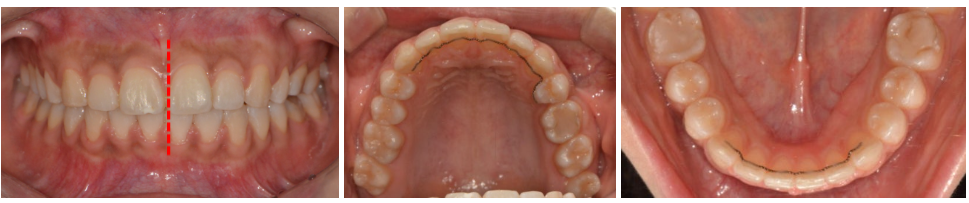

상하악 치열의 중심선 일치

좌측 어금니 교합 안정화

상악 전치 돌출감 자연스럽게 개선